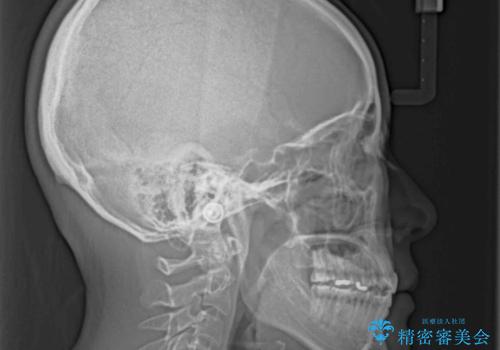

【モニター】狭い上顎歯列とオープンバイト 急速拡大装置を用いた矯正治療

- 前歯の開咬を気にして来院された患者様です。

上顎歯列が狭窄していたため、急速拡大装置により上顎骨を側方に拡大し、その後インビザラインにて矯正治療を行うこととしました。

舌の突出癖が開咬の原因であったので、改善のための舌トレーニングを行っていただきました。

舌トレーニングは後戻りにも大きく影響するため、とても重要なトレーニングです。